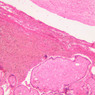

The wall of the uterine tube consists of three layers; a mucosa, a muscularis, and an adventitial/serous coat (B-96 [2.5x, 10x-labeled, 20x, 40x] [2.5x, 10x, 20x, 40x]; B-97, monkey uterus [2.5x, 10x, 20x, 40x]). The mucosa is organized into folds that vary in their degree of complexity with the tube regions. The mucosa is lined by a simple columnar epithelium consisting of two cell types, ciliated and non-ciliated, secretory (B-93 [10x, 20x, 40x-labeled]). The mucosal lamina propria consists of somewhat loose connective tissue and is highly vascular. No muscularis mucosae are present. The muscularis consists of two layers of smooth muscle, the inner being oriented in a circular fashion and the outer longitudinally.

The structure of the uterine tube is under the control of, and responds to, cyclic changes in the levels of steroid hormones. Structural alterations to provide favorable transport for the oocyte commence anew with the beginning of each cycle and peak at mid-cycle just before ovulation. These include increases in height and number of the ciliated cells as well as active secretion in the secretory cell. For the remainder of the cycle thereafter, dedifferentiation occurs. The cyclic changes occur to a greater extent in the upper ampulla and infundibulum. The margin of the infundibulum is drawn out into numerous finger-like processes called fimbrae. Microscopic examination of these will reveal that within the lamina propria are numerous large blood vessels, especially veins, as well as bundles of smooth muscle forming an intervening network. At the time of ovulation, the vessels become enlarged with blood, causing turgidity, which when combined with smooth muscle contraction brings the infundibular opening into close apposition with the ovarian surface.